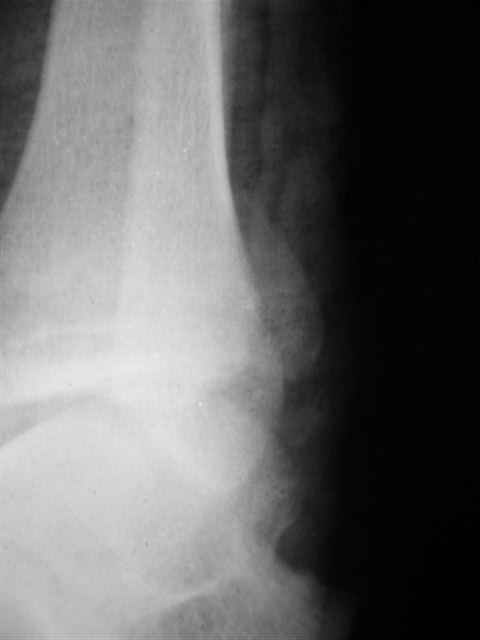

В первом письме я упомянул о закрытом повреждении правого голеностопного сустава, эверсионно-пронационный механизм травмы - перелом внутренней лодыжки( поперечный, на уровне суставной щели) и отрывной перелом бугорка Chaput. После обработки открытых переломов бедра и большеберцовой кости в эту же сессию перелом внутренней лодыжки фиксировал двумя расходящимися спицами, бугорок Chaput двумя тягловыми винтами 3,5 мм. Раны заживают благополучно. Учитывая повреждение наружной группы мышц, активное разгибание в голеностопном суставе ограничено. Пассивная + пассивно-активная мобилизация голеностопного сустава с физиотерапевтом.

Я предупреждал, что ничего сверхъестественного. Каюсь, что одна из спиц прошла несколько дальше, чем нужно было, но главное - перелом стабилизирован и больной работает суставом в полном объёме, несмотря на представленную раннее травму коленного сустава.